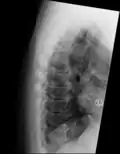

"Melted candle wax" appearance of calcification and ossification in diffuse idiopathic skeletal hyperostosis (DISH). Note the preponderance on the patient's left side (right side of image). -